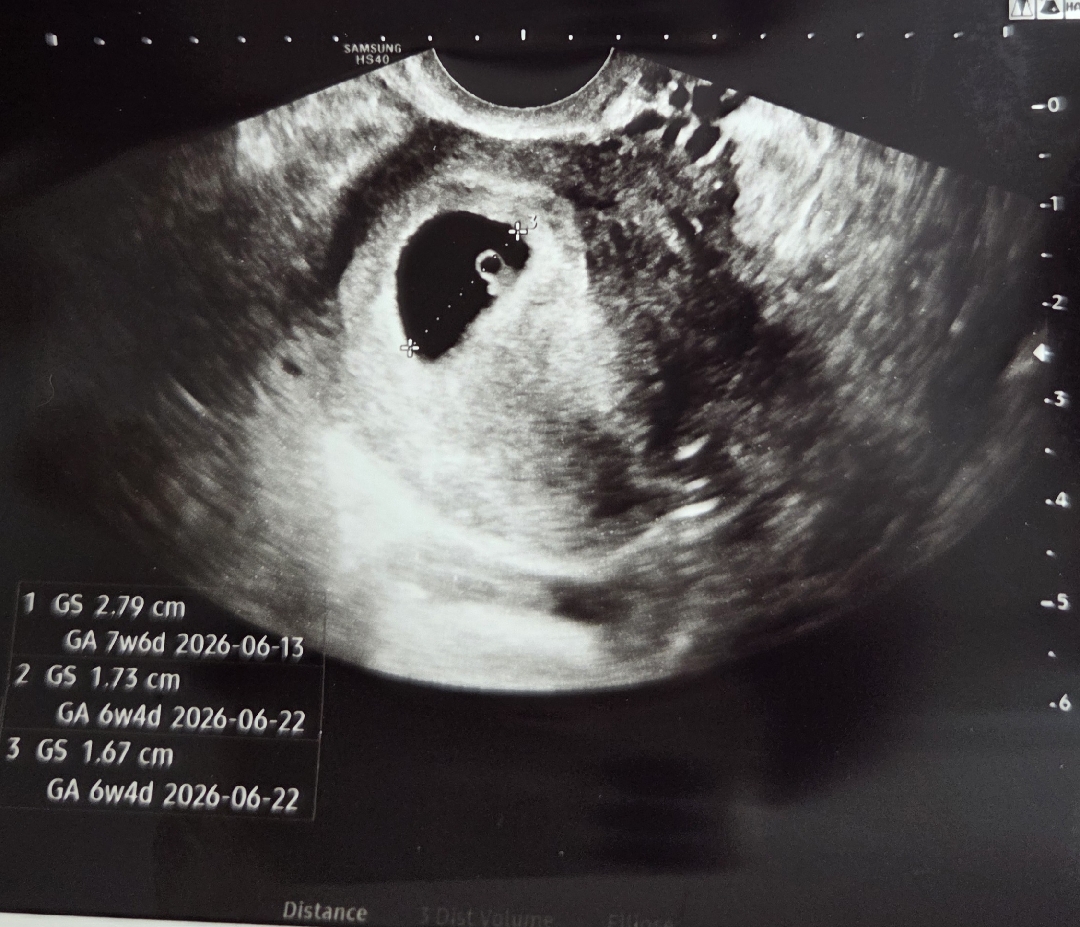

아기집 내부!!의 피고임

오늘 초음파를 봤는데 아기집이 주수보다 많이 크더라구요 아기는 6주4일인데 아기집은 7주-8주 정도로요ㅠㅠ (아기 성장이 느린 게 아니고 아기집이 너무 커요) 아기집 내부 피고임이 예상된다고 하시는데 아기집 주변 말고 내부에 피고임이 있었던 분도 계신가요? 선생님께서는 전~혀 문제없고 건강한 임신이니 피고임은 그냥 기다리면 된다고 하셨는데요..! 인터넷 여기저기 찾아보면 안 좋다는 글밖에 없어서요..ㅠㅠ 비슷한 경험 있는 분들 댓글 많이 부탁드립니다🥲 초음파 다른 각도로 보면 제가 올린 사진보다 아기집이 두배 커요..